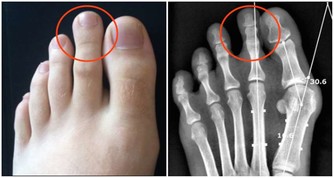

在許多前列腺癌病人中,病灶轉移很常見,大約有三分一的病人在初次就醫時就已有淋巴結轉移,多發生在骼內、骼外、腰部、腹股溝等部位。可引起相應部位的淋巴結腫大及下肢腫脹。血行轉移多見於骨骼,如骨盆、骶骨等,或內臟,如肺、肝、腦等。(參考網站:聞康男性)